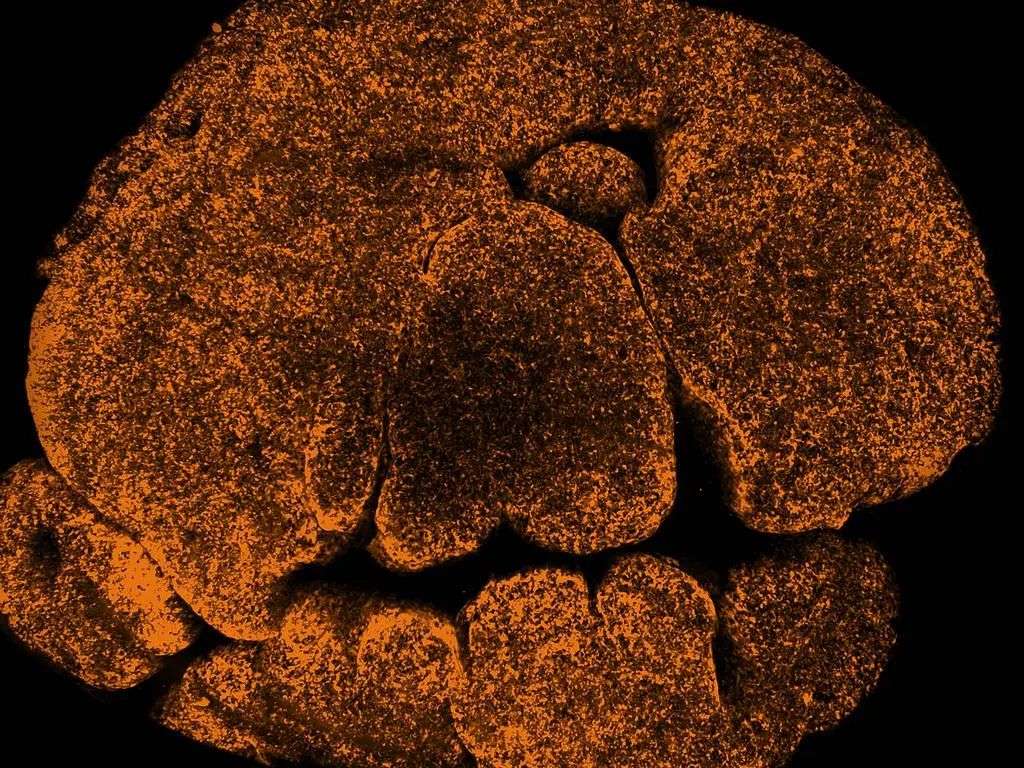

(这组圆点让人想起万圣节南瓜,它们代表着构成胸腺的细胞。)

如今,通过使用新的成像技术,团队首次窥探到完整的胸腺结构,并发现了这个问题的部分原因。

WEHI的成像负责人赵柯林(Kelin Zhao)博士说,这些发现首次展示了疤痕形成如何成为胸腺功能障碍的障碍。

她表示:“通过捕捉这些细胞团的活动,并展示它们如何导致胸腺功能丧失,我们完成了前所未有的工作。”